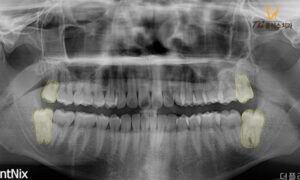

위 환자분께서는

위아래의 사랑니가 있는데

최대한 빨리 뽑았으면 좋겠다며

본원으로 내원해 주셨습니다.

일단 위쪽의 사랑니는 오래전부터 맹출 했고,

그 부위로 음식물도 잘 끼고,

치간칫솔이 잘 안 들어가서

관리가 어렵다고 말씀해 주셨습니다.

아래쪽은 아직 나진 않았는데

엑스레이 상 사랑니의 방향이 똑바른 방향이라

쉽게 뽑을 수 있을 거라고

생각했다고 하셨는데요.

환자분의 상태에서 양쪽 위

사랑니의 경우 올바른 방향으로

머리 부분이 노출된 상태였기 때문에

단순 발치를 진행하여 간단히 발치가 가능합니다.

하지만 양쪽 아래 사랑니의 경우

잇몸뼈 안에 묻혀있는 매복 사랑니의 형태이며,

특히 왼쪽 아래의 사랑니의 뿌리를 보시면

휘어있는 모습이 관찰됩니다.